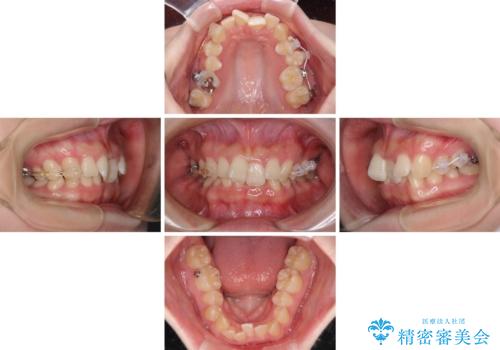

カリエール・ディスタライザーを使用している期間、反対側はワイヤー矯正により叢生を解消していくこととしました。

奥歯の咬み合わせを改善しながら、並行してインビザラインで歯列を整えることとしました。